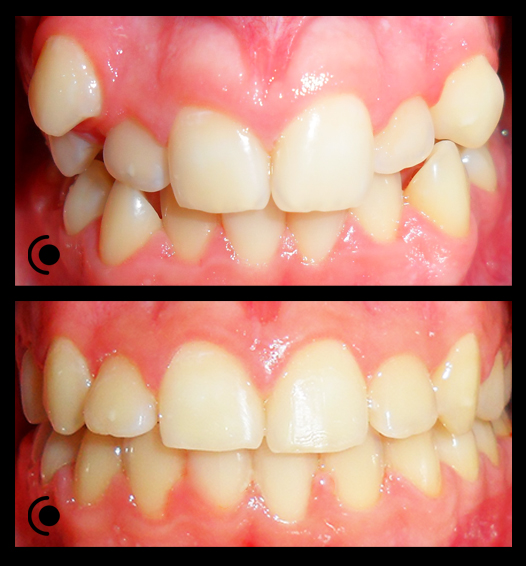

O našoj kvaliteti najbolje govore naši rezultati!

Centar za ortodonciju Petra Džapo